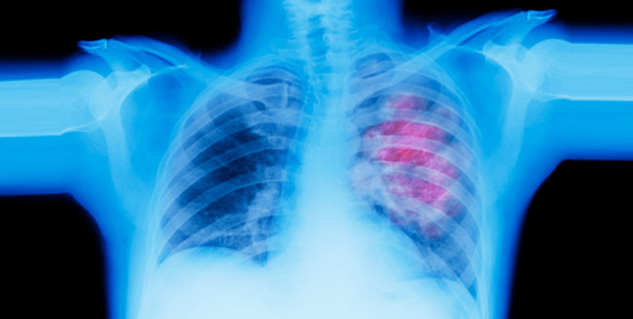

जिस तेजी से प्रदूषण बढ़ रहा हैए उसी तेजी से फेफड़ों से सम्बंधित समस्याएं भी बढ़ रही हैं। यहीं नहीं फेफड़ों के कैंसर भी तेजी से अपने जड़ जमा रहे हैं। फेफड़ों के कैंसर के कारण मरीज को सांस लेने, बातें करने, काम करने आदि तमाम चीजों में समस्याएं आती हैं। ऐसे में यह जानना जरूरी है कि फेफड़े के कैंसर के मरीज को कैसी सतर्कता बरतनी चाहिए। साथ ही यह भी जानना आवश्यक है कि फेफड़े के कैंसर के बुनियादी लक्ष्ण क्या क्या हैंघ् असल में धूम्रपान भी इसकी एक बड़ी वजह है।

यदि फेफड़े के कैंसर के बारे में शुरुआती चरण में ही पता चल जाए तो इससे निजात पाया जा सकता है। फेफड़े के कैंसर के चलते श्वास लेने में किस किस प्रकार से समस्याएं आती हैं-